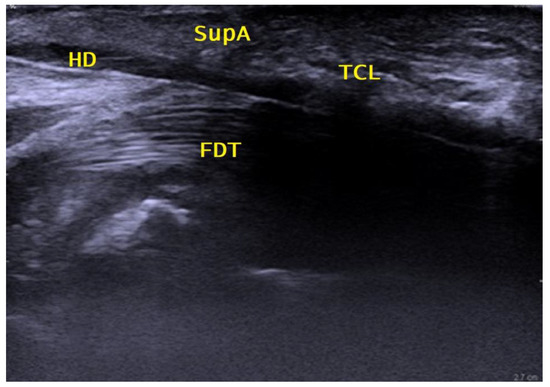

Another deposit of 1 to 2 mL of local anesthetic was injected to open up the distal carpal tunnel space by hydrodissection. The 27 G cannula was then removed. Under continuous hydrodissection with local anesthetic, a 18 G epidural cannula (slightly bent to match the curved undersurface of the TCL) was then inserted through the same entry point, passed over the SPA and through the palmar aponeurosis under the distal edge of the TCL into the carpal tunnel space. Under continuous real-time ultrasound control, it was then advanced dorsally to the TCL and palmar to the flexor tendons along the safe zone from distal to proximal, exiting at a point 2 cm proximal to the wrist crease, facilitated by slight dorsal extension of the wrist, as shown in Figure 2. The position of the cannula was checked and could be corrected continuously longitudinally and axially over the whole length of the carpal tunnel by sonography to exclude any malpositioning due to movement of the wrist or fingers and the thereby potential positional change of the median nerve in the carpal canal.

Figure 2.

Sagittal proximal palmar view. HD = hydrodissected area; FDT = flexor digitorum profundus and superficialis tendons; TCL = transverse carpal ligament; SupA = superficial palmar aponeurosis.